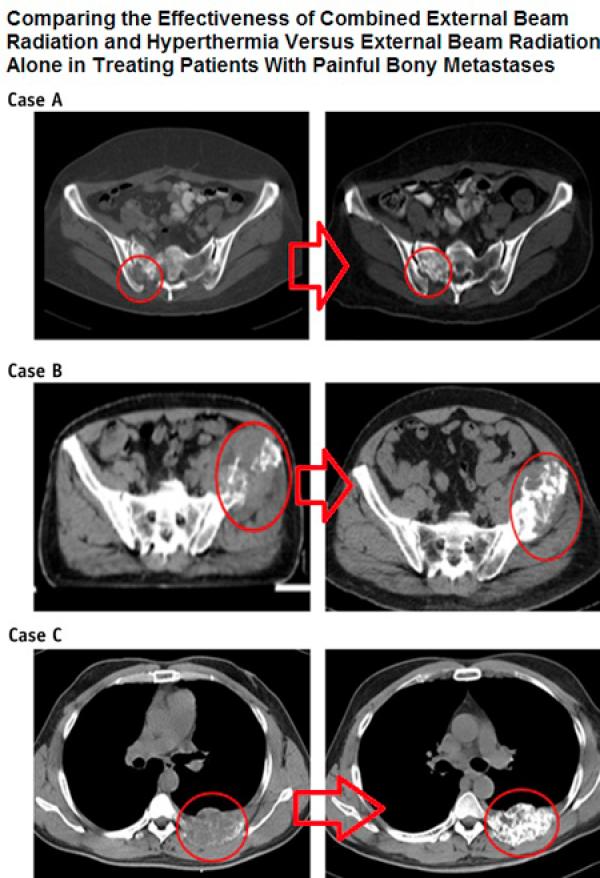

Ağrılı Kemik Metastazında Radyoterapiye Derin Doku RF Hipertermi Eklenmesi Tedavinin Başarısını Arttırıyor

Tamamlayıcı Kanser Tedavisi KliniğiDerin Doku RF Hipertermi & İmmunoterapi & Fitoterapi & Ozon Tedavisi & ElektrokemoterapiKemik metastazı, kanser hastalarında sıklıkla görülen...